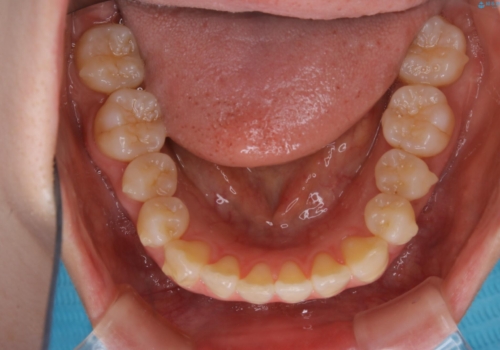

- 前歯のがたつきが気になるとご相談にいらした方です。右側前歯部のクロスバイトの他、左側にもシザーズバイトが認められたため、インビザラインにて治療を行いました。出産直後のため、ご自身の時間がなかなか取れないとの事で、最小限の来院回数で治療を勧められるように計画しました。

患者様ご自身で使用時間をしっかり管理して頂くことを条件に、最低限の来院回数で治療を進めていきました。20時間以上の使用を厳守して頂けたことで、少ない来院回数にて治療を終了することが出来ました。前よりも噛みやすくなったと大変喜んでいただけました。